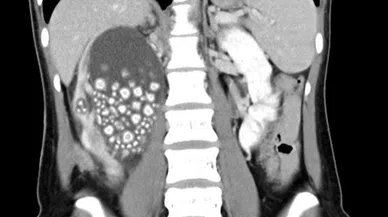

Böbrek Taşı Haberleri

Bu sayfada güncel gelişmeleri takip edenler için Böbrek Taşı ile ilgili en son gelişmeler ve son dakika Böbrek Taşı haberleri sunulmaktadır. Böbrek Taşı videoları, Böbrek Taşı fotoğrafları ve Böbrek Taşı haberleri